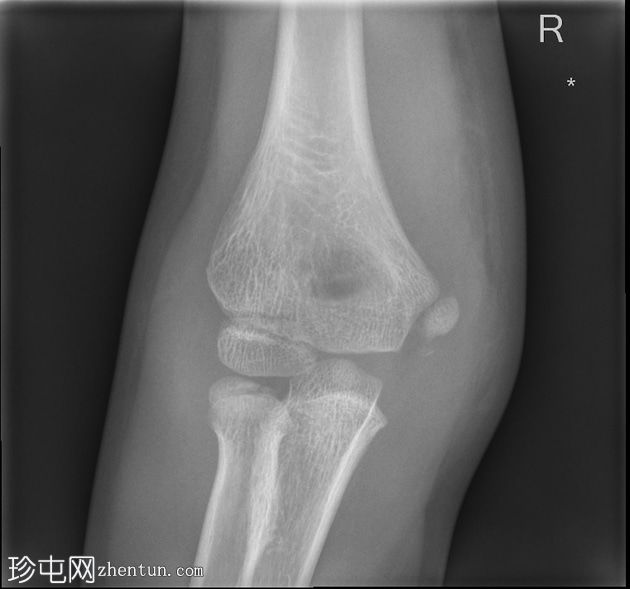

肘关节X线片

X线片

正位片

2.jpg

内上髁附近可见骨碎片,内上髁轻度移位。上方软组织中度肿胀,前脂肪垫隆起,提示关节积液。影像表现符合内上髁撕脱性骨折。关节对位正常。

桡骨头骨骺可见正常变异裂隙。